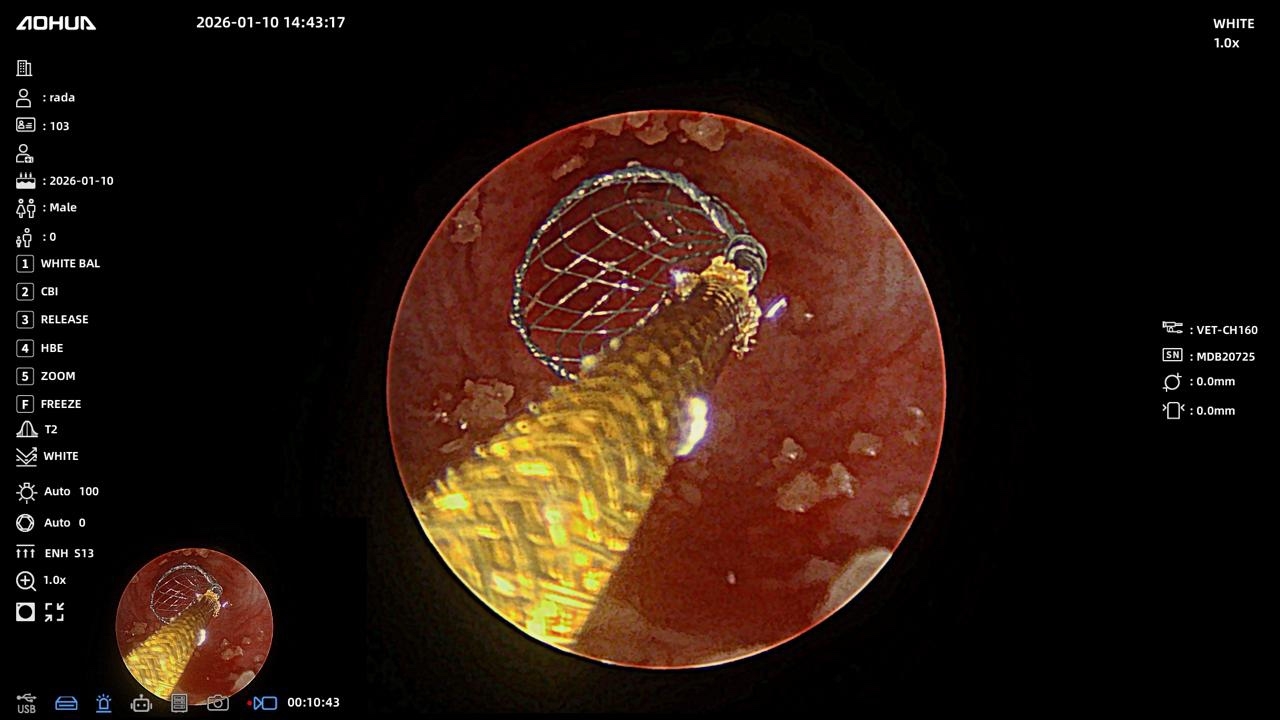

Нас тепло приняли в Эндовет, провели все необходимые обследования и на следующий же день была назначена операция. Нашей таксе почти 10 лет, опасались, как она перенесет наркоз. Но после беседы с Александром Владимировичем стало спокойнее. Операция длилась 3 часа, были удалены камни из почек и мочеточника, установлены стенты. Все прошло более чем хорошо. 2,5 дня стационара, 2 небольших прокола, собака чувствует себя хорошо и быстро восстанавливается. Большое спасибо команде клиники, анестезиологу, работникам стационара, регистратуры и, конечно же, Александру Владимировичу за такой тяжёлый и нужный труд. До сих пор не верится, что мы дома и все закончилось благополучно благодаря Вам)